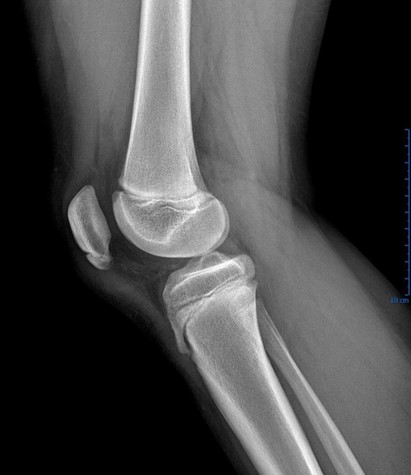

Case courtesy of Dr. Alan Jossimar Zavala Vargas, Radiopaedia.org. From the case rID: 80636

Sinding-Larsson-Johansson Disease

This eponymous condition is another example of a juvenile apophysitis, pathophysiologically similar to Osgood-Schlatter. It occurs from the overuse of the inferior growth plate of the patella, resulting in inflammation and calcification. Excess stress from muscle pull over the apophysis during growth is associated with this condition. Patients present with inferior patellar pain with flexion when the patella is force loaded, such as running or jumping. There is often associated swelling and limitations on activity and/or performance. Plain radiographs can be helpful to differentiate bipartite patella from patellar fracture.17 US has been shown to be effective in identifying the condition. There are no long-term sequelae, and participation can be continued as tolerated. Pain may be persistent and may respond to NSAIDs. Similar to other apophysitis, rest in addition to stretching and strengthening can help improve symptoms. In some patients, prolonged rest is the best treatment.17 Steroid injections should not be performed.9